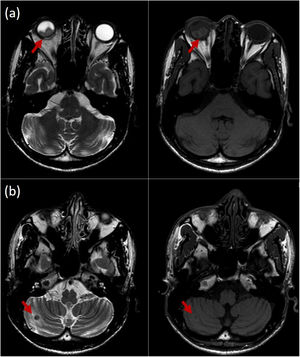

El paciente fue ingresado para estudio. La resonancia magnética orbitaria evidenció un desprendimiento completo de retina del ojo derecho secundario a lesiones retinianas elevadas quísticas, que ocupaban los cuadrantes inferiores del globo ocular (fig. 2A). Los hallazgos descritos plantearon el diagnóstico diferencial entre tumoración quística retiniana, quistes parasitarios y, menos probable, quistes intrarretinianos hemorrágicos. También se apreció una lesión ocupante de espacio en el hemisferio cerebeloso derecho (fig. 2B).

A) Resonancia magnética orbitaria en T2 y T1, que evidenció lesiones retinianas con realce liso de sus paredes, que ocupaban los cuadrantes inferiores del globo ocular. B) Lesión de 8mm en el hemisferio cerebeloso derecho, hipointensa en T2, con relace en anillo y ligeramente hiperintensa en T1.